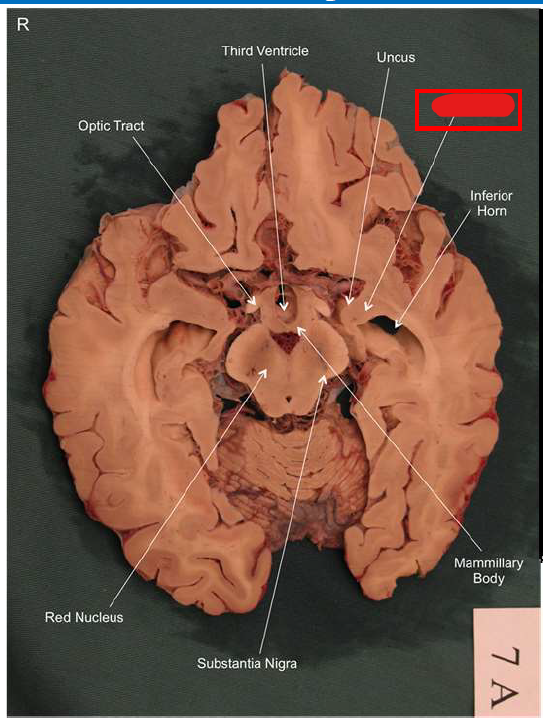

What is the fornix of the hippocampus?

Hippocampus output pathway (C-shaped)

Connects hippocampus to hypothalamus/mamillary bodies

Carries information to and from hippocampus

Important for memory consolidation and retrieval

What is this?

hippocampal fornix